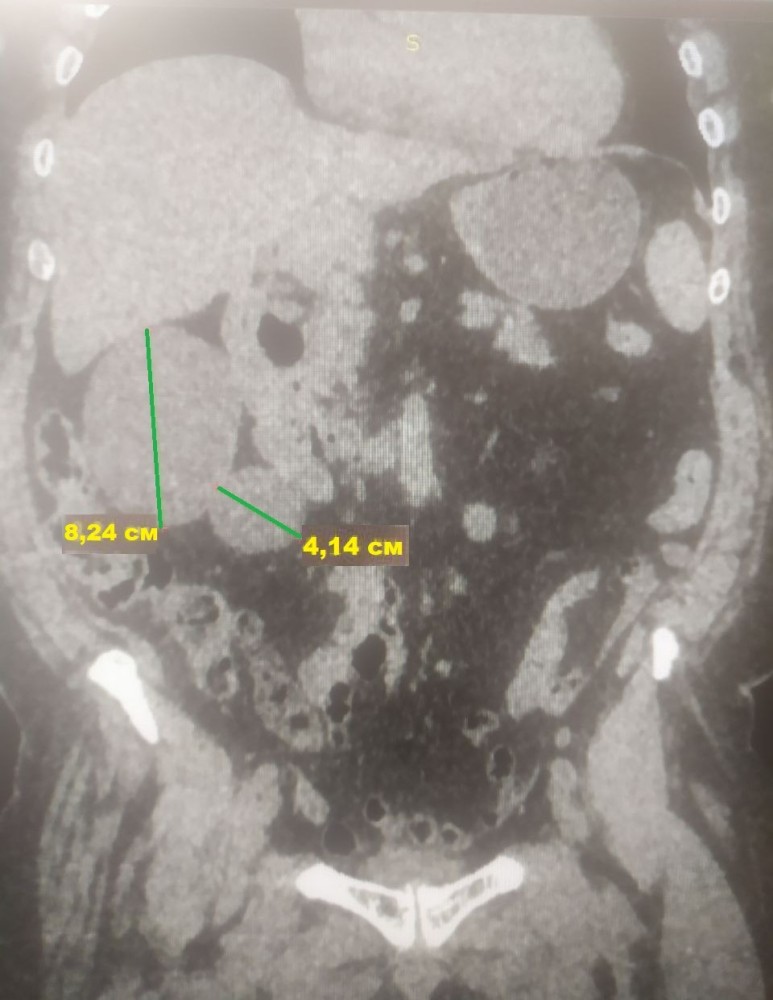

У результаті проведених обстежень лікарі діагностували солітарні кісти правої нирки 8,24 см та 4,14 см в діаметрі (новоутворення з тонкими стінками, заповнені рідиною).